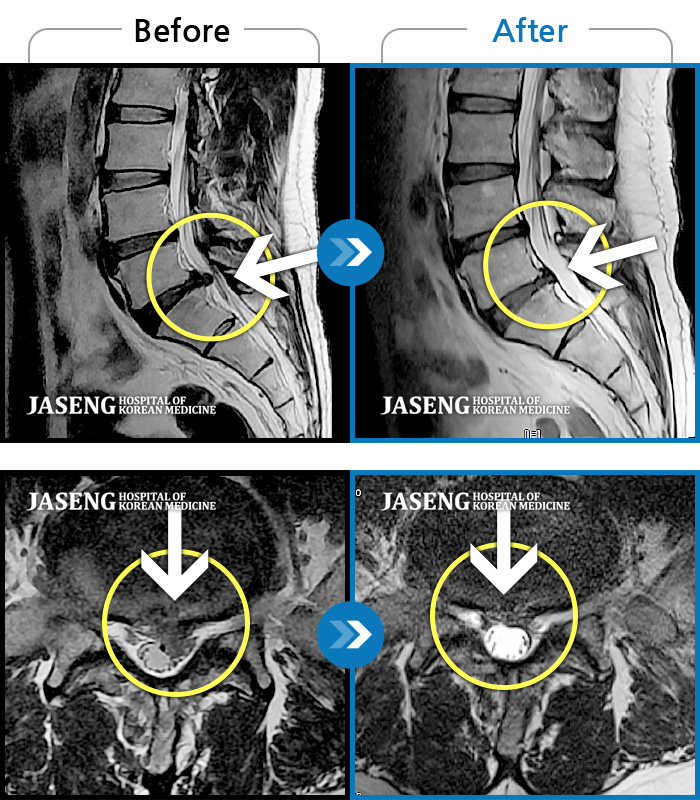

[뱸] 19.11.28~25.05.06